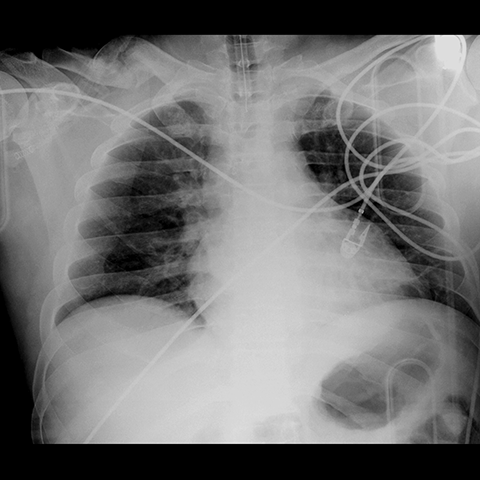

Portable AP Chest Radiograph [3 of 3]

Lines